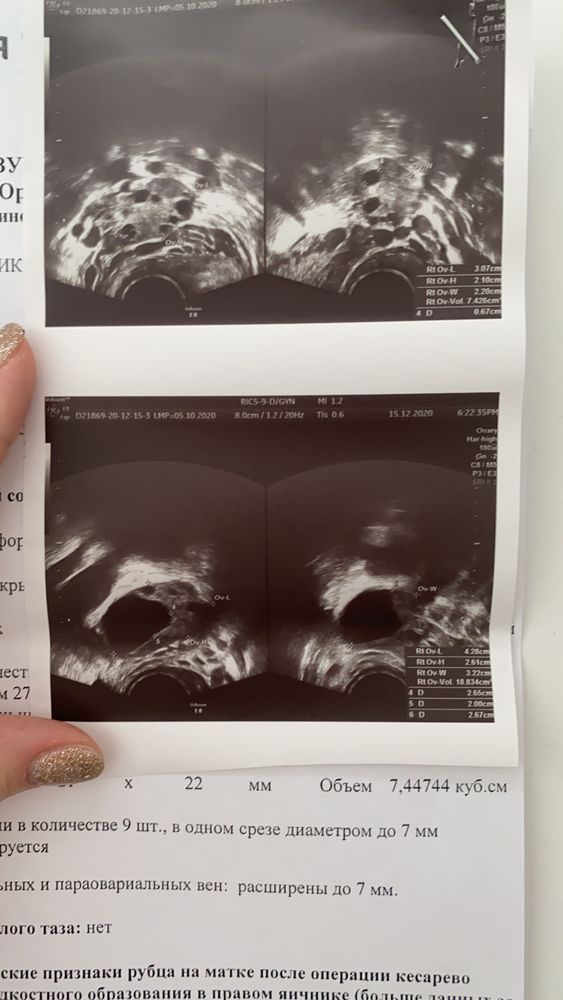

Девочки , посмотрите , 17 дц узи

Решила сходить на узи т.к мучали боли внизу живота .

фото узи и заключение прилагаю .

Ну пишут, что ДФ не лопнул и перерос в кисту, но всё так предположительно у них, неуверенно как-то. Ну и пошёл в регресс, видимо, и боли пропали.